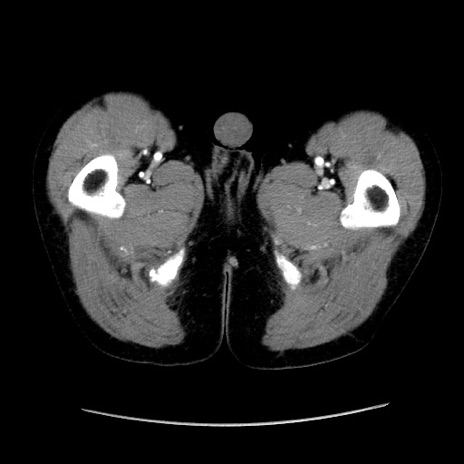

症例37(横断像)

【症例】40歳代 男性

【主訴】腹痛

【現病歴】4時間ほど前に電車に乗車中に臍部上より腹痛出現。徐々に増悪し起立困難となり、救急外来受診。生ものは数日食べていない。今朝お雑煮を食べた。

【身体所見】BT 36.8℃、BP 117/84mmHg、HR 91/min、SpO2 97%、苦悶様、腹部:臍上部広範囲圧痛あり、反跳痛±

【データ】WBC 8100、CRP 0.03